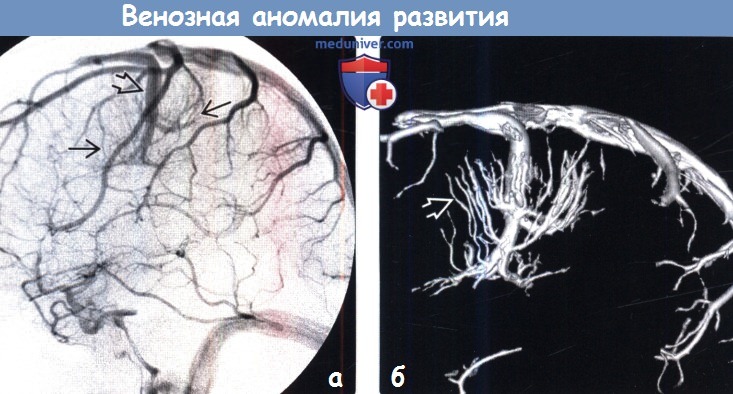

Мр картина венозной ангиомы левой гемисферы мозжечка - 96 фото